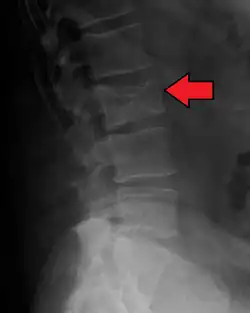

The diagnostic examination of a person with suspected multiple myeloma typically includes a skeletal survey. This is a series of X-rays of the skull, axial skeleton, and proximal long bones. Myeloma activity sometimes appears as "lytic lesions" (with local disappearance of normal bone due to resorption) or as "punched-out lesions" on the skull X-ray ("raindrop skull"). Lesions may also be sclerotic, which is seen as radiodense.[76] Overall, the radiodensity of myeloma is between −30 and 120 Hounsfield units (HU).[77] Magnetic resonance imaging is more sensitive than simple X-rays in the detection of lytic lesions. An MRI may supersede a skeletal survey, especially when vertebral disease is suspected. Occasionally, a CT scan is performed to measure the size of soft-tissue plasmacytomas. Nuclear Medicine Bone scans are typically not of any additional value in the workup of people with myeloma (no new bone formation; lytic lesions not well visualized on nuclear bone scan).

Pathological fracture of the lumbar spine due to multiple myeloma -

Bone pain affects almost 70% of people with multiple myeloma and is one of the most common symptoms.[2]: 653 [23] Myeloma bone pain usually involves the spine and ribs and worsens with activity. Persistent, localized pain may indicate a pathological bone fracture. Involvement of the vertebrae may lead to spinal cord compression or kyphosis. Myeloma bone disease is due to the overexpression of receptor activator for nuclear factor κ B ligand (RANKL) by bone marrow stroma. RANKL activates osteoclasts, which resorb bone. The resultant bone lesions are lytic (cause breakdown) in nature. They are best seen in plain radiographs, which may show "punched-out" resorptive lesions (including the "raindrop" appearance of the skull on radiography). The breakdown of bone also leads to the release of calcium ions into the blood, leading to hypercalcemia and its associated symptoms.[24]